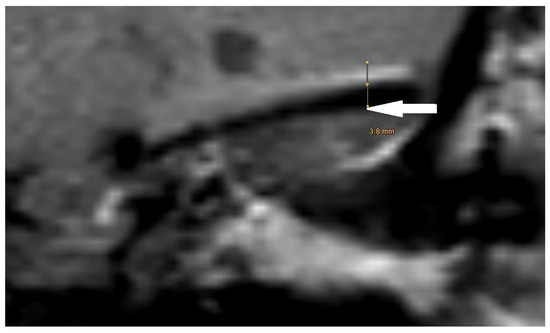

| PORP | 2.0 mm | 3.1 mm | 5.4 mm |

| TORP | 3.6 mm | 4.7 mm | 7.2 mm |

| Mesh | 0.1 mm | 3.6 mm | 5.8 mm |